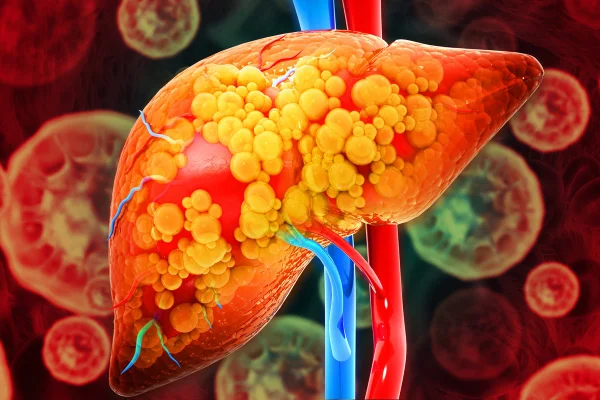

A esteatose hepática é popularmente conhecida como gordura no fígado

A condição de gordura no fígado acomete 30% da população mundial